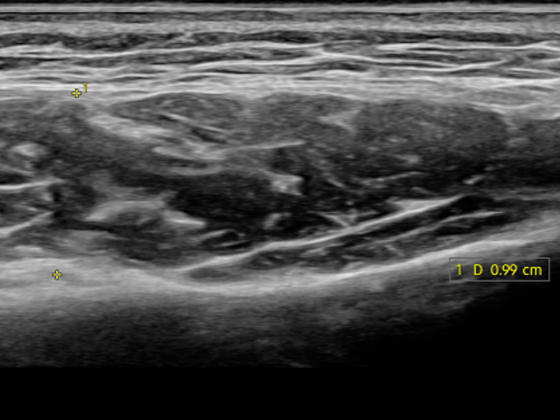

초음파를 통해 근육층을 확인하여 정확한 근육 위치에 안전하게 시술하는 초음파 보톡스

일반적인 보톡스 시술은 담당의가 피부를 만져보고 판단하여 진행됩니다. 이 과정에서 의사의 감만으로 시술을 진행할 확률이 높기때문에 부작용이 생기거나 시술효과가 떨어지기도 합니다. 반면에 초음파 보톡스는 환자의 근육과 지방의 양, 크기를 모니터를 통해 확인하며 시술하기 때문에 부작용을 최소화합니다.

근육의 위치·두께를 확인해 개인에게 맞는 용량/포인트를 설계합니다.

STEP 02마취 및 근육·지방 두께 체크필요 시 도포/국소마취 후, 초음파로 근육·지방층의 위치와 두께를 확인합니다.